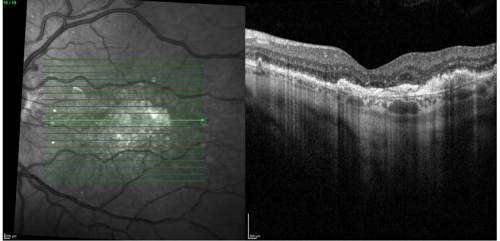

On clinical examination and multimodal imaging—including optical coherence tomography (OCT) and fundus autofluorescence (Figures 1 and 2A)—we confirmed a GA lesion with hyperfluorescent edges, a hallmark of progression, in the right eye. Comparing current imaging of the patient’s right eye with earlier records demonstrated clear lesion growth (Figure 2). These prognostic factors, combined with his functional symptoms, made the patient an excellent candidate for therapy with an FDA-approved complement inhibitor. Prior to the availability of complement inhibitor therapy for GA, management of this condition was limited to monitoring every 6 months, with no effective intervention beyond lifestyle measures.